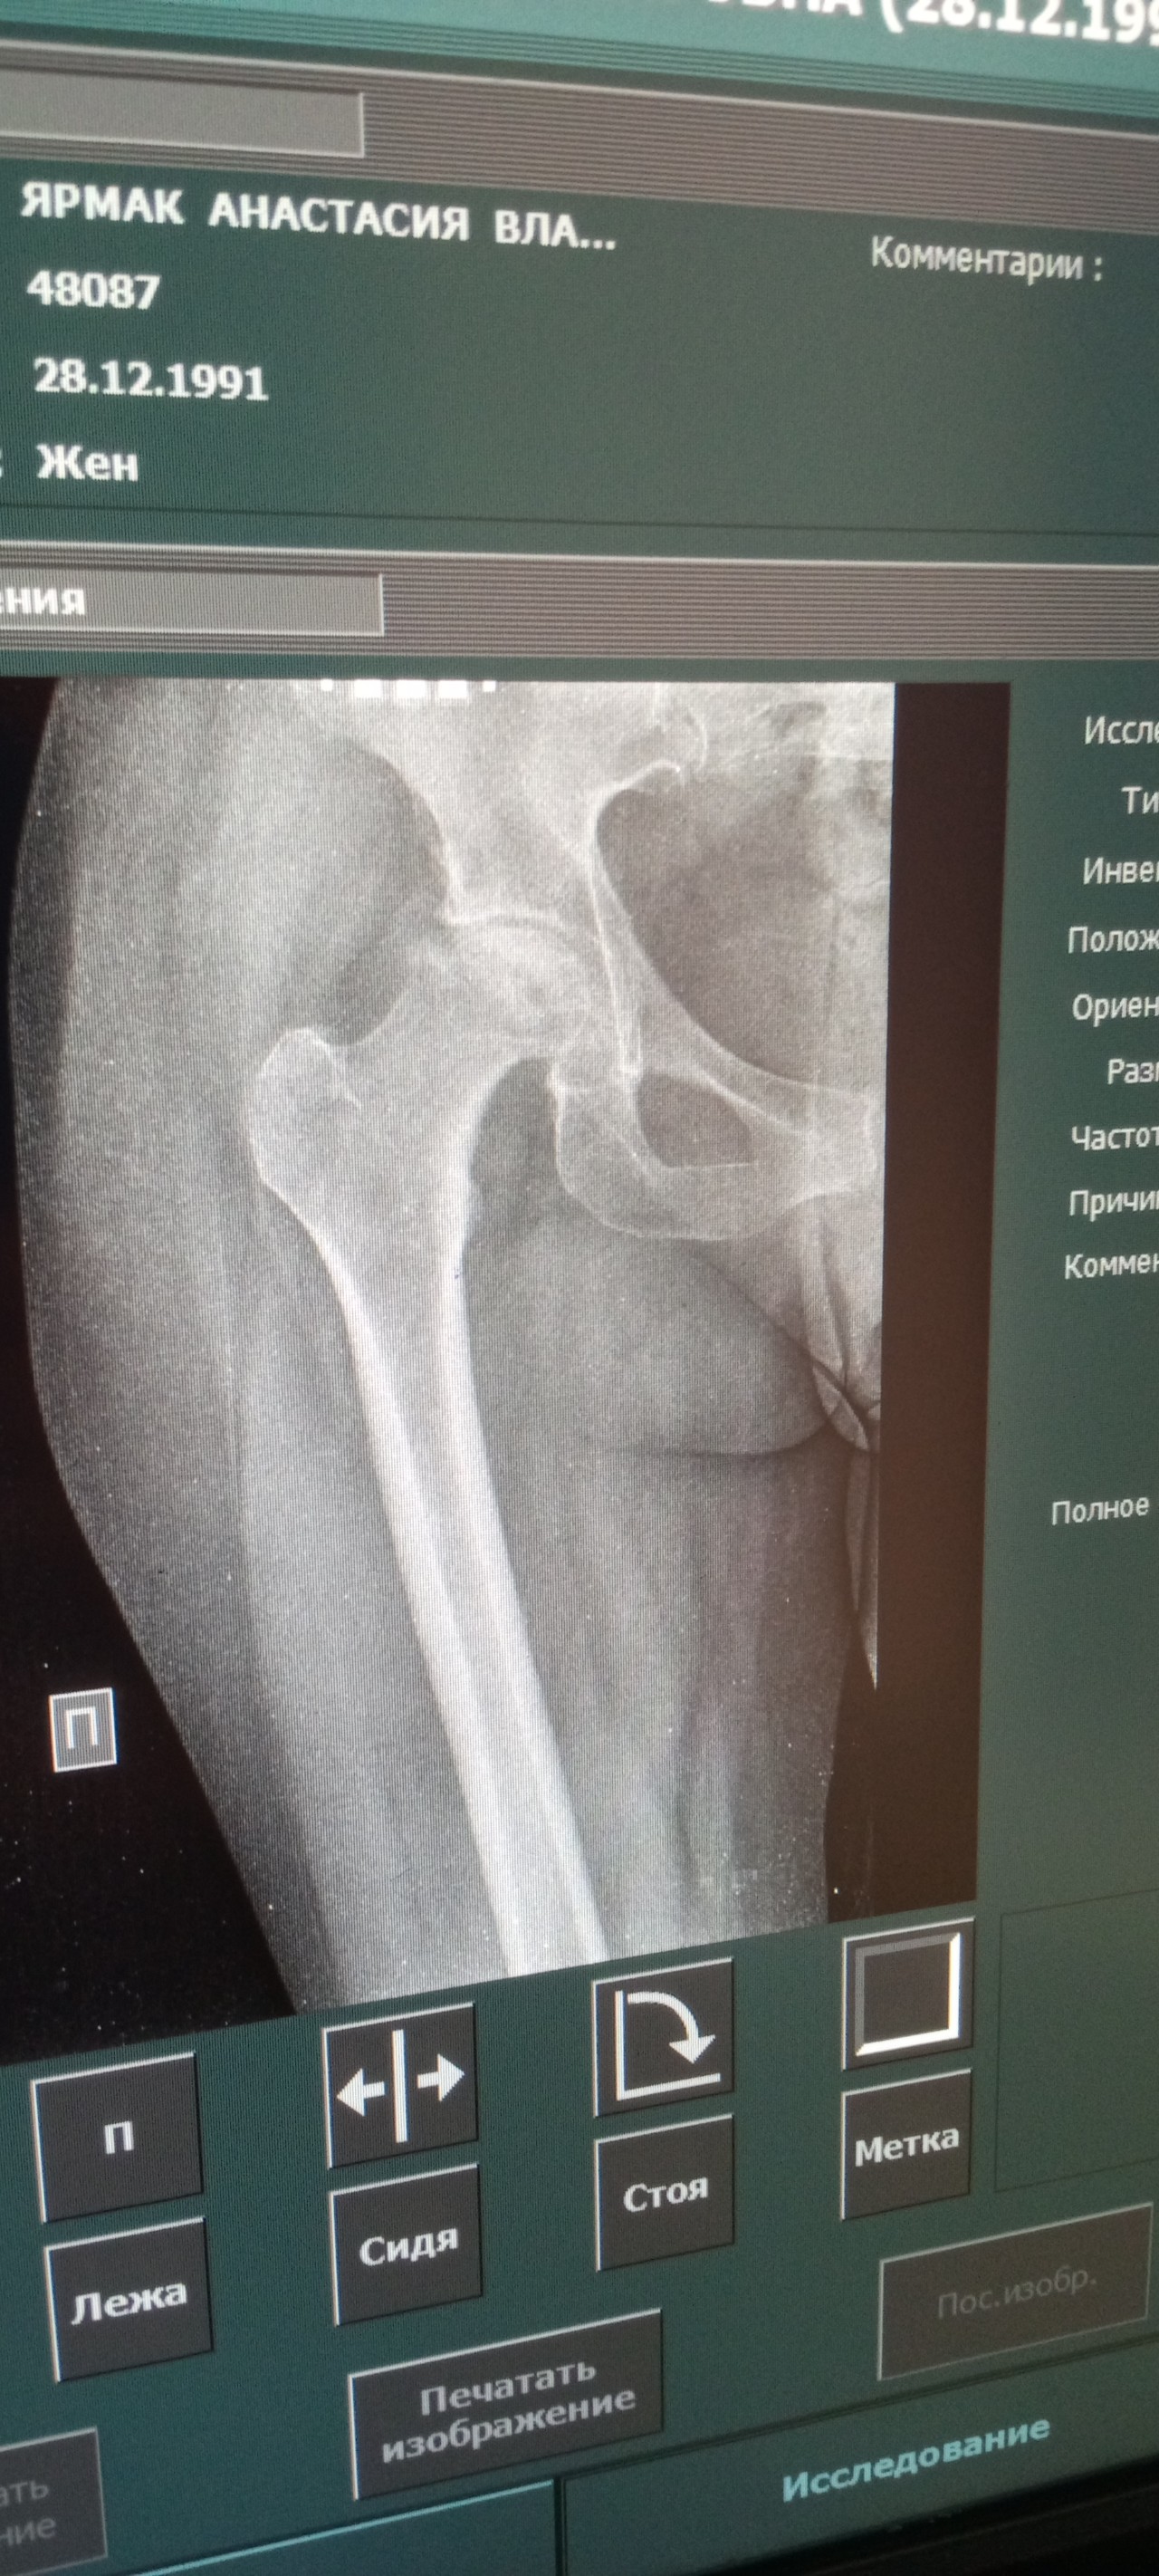

Здравствуйте, длительное время юеспоклит боль в бедре. Больно ходить. Иногда ослабевает, но зачастую усиливается. Сделала рентген снимок. Прикладываю. Подскажите насколько все серьезно и можно ли это вылечить медикаментозно? Какие мои действия?